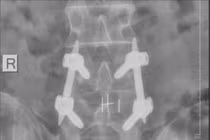

Sau khi hội chẩn, người bệnh được BSCKII Hà Xuân Tài, Trưởng khoa Ngoại Thần kinh trực tiếp phẫu thuật bằng phương pháp nội soi cột sống – một kỹ thuật tiên tiến, ít xâm lấn.

Sau phẫu thuật, người bệnh hồi phục tốt, có thể đi lại và vận động nhẹ nhàng sau 2 ngày. Sau 1 tuần theo dõi, các triệu chứng đau trước mổ không còn, người bệnh được xuất viện trong tình trạng ổn định.